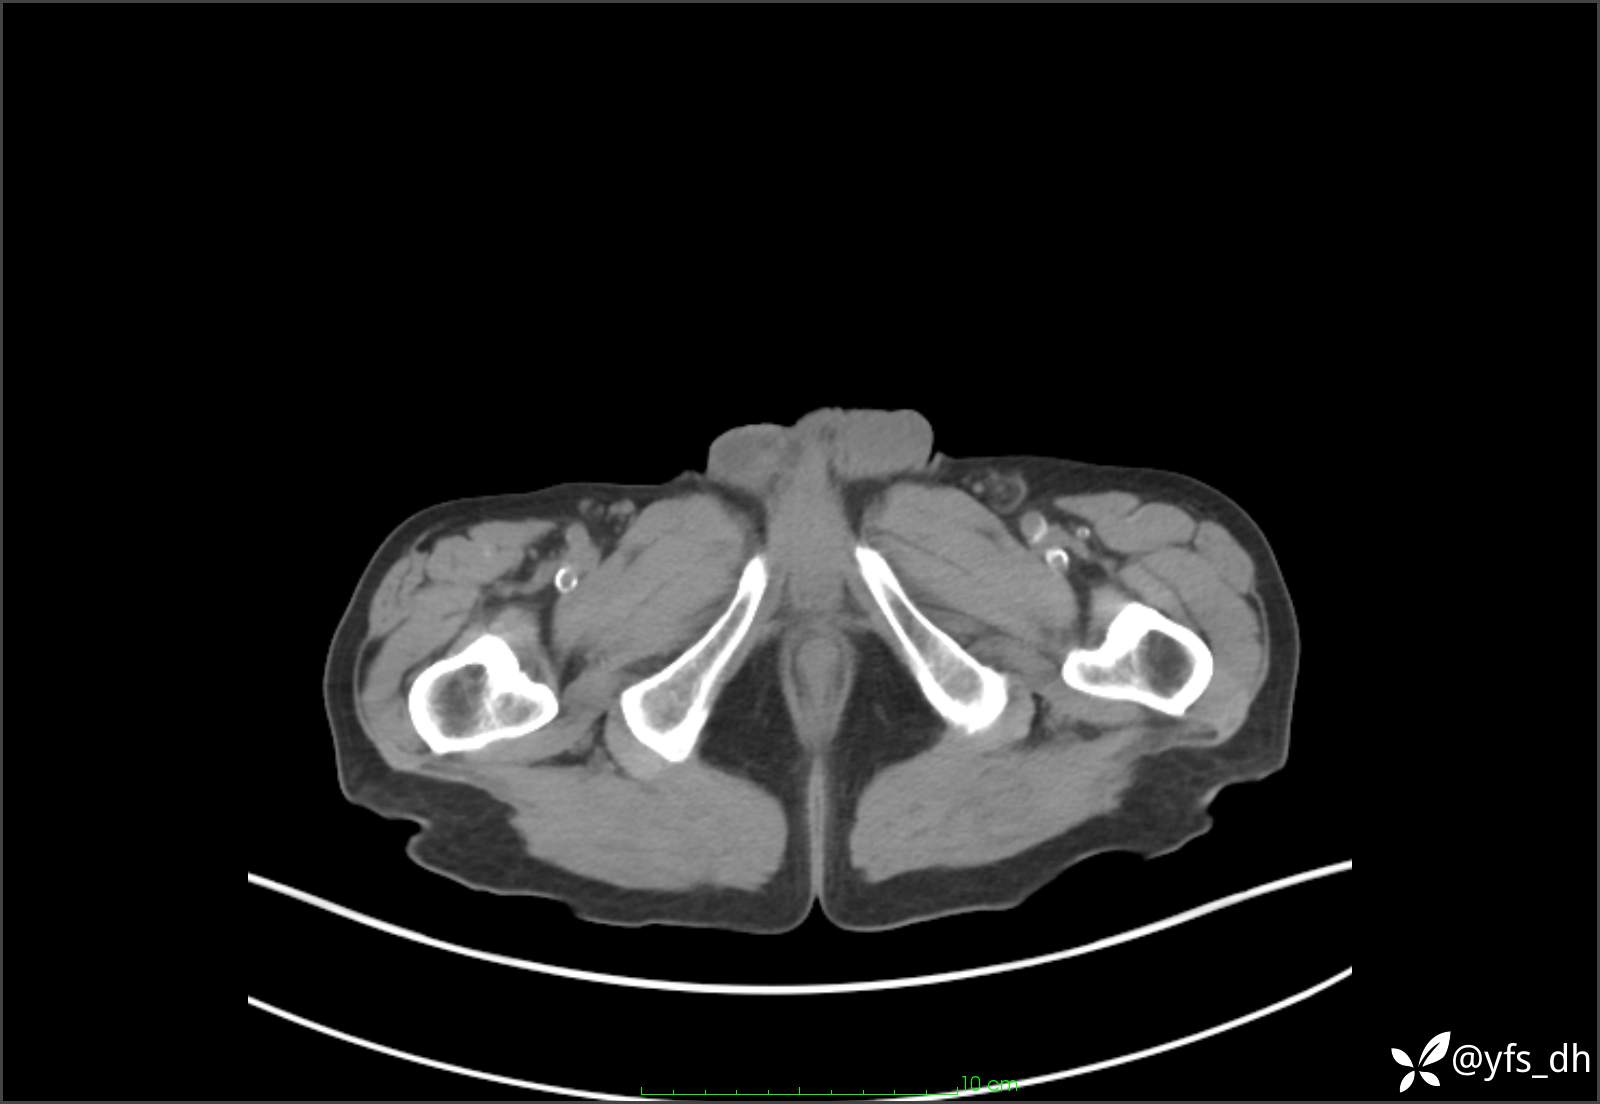

1.简要病史:患者4天前突发上腹部疼痛不适,但可以忍受。3小时前饭后突然加重,不能忍受后就诊。

2.简要手术记录:术中见腹盆腔大量肠液及粪便,乙状结肠中下段见一约3cm的破口。